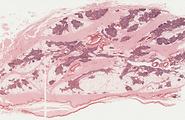

Amigdala palatina- H-E- 20X